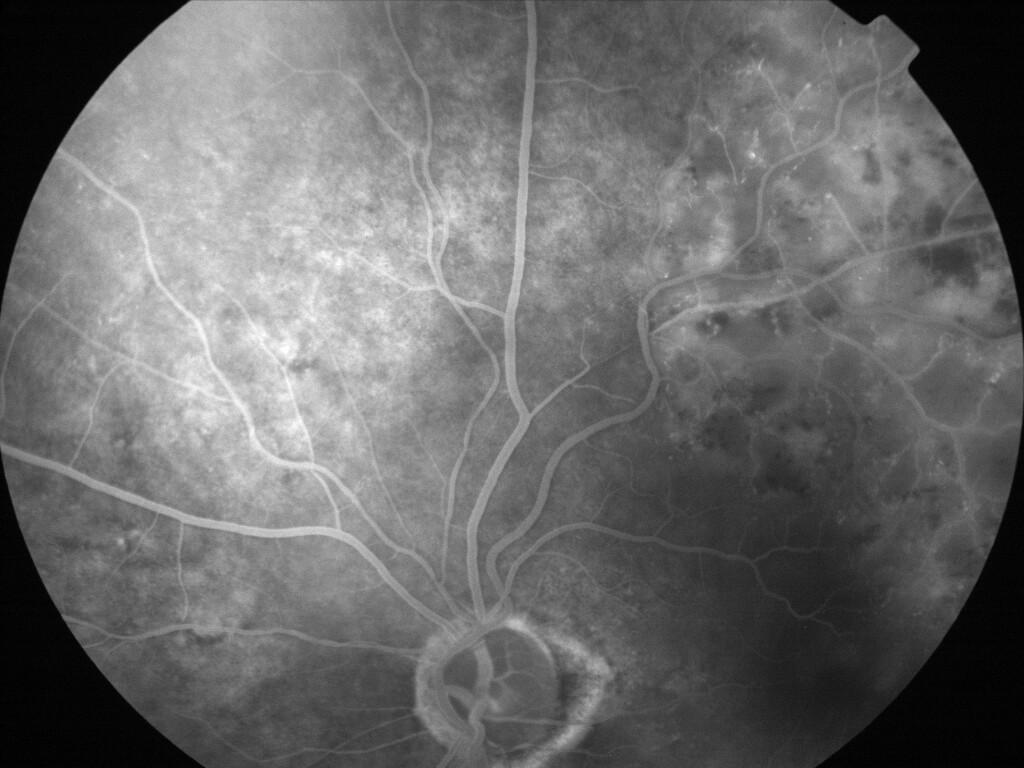

OCCLUSION DE BRANCHE DE LA VTS DE FORME ISCHEMIQUE MAJEURE